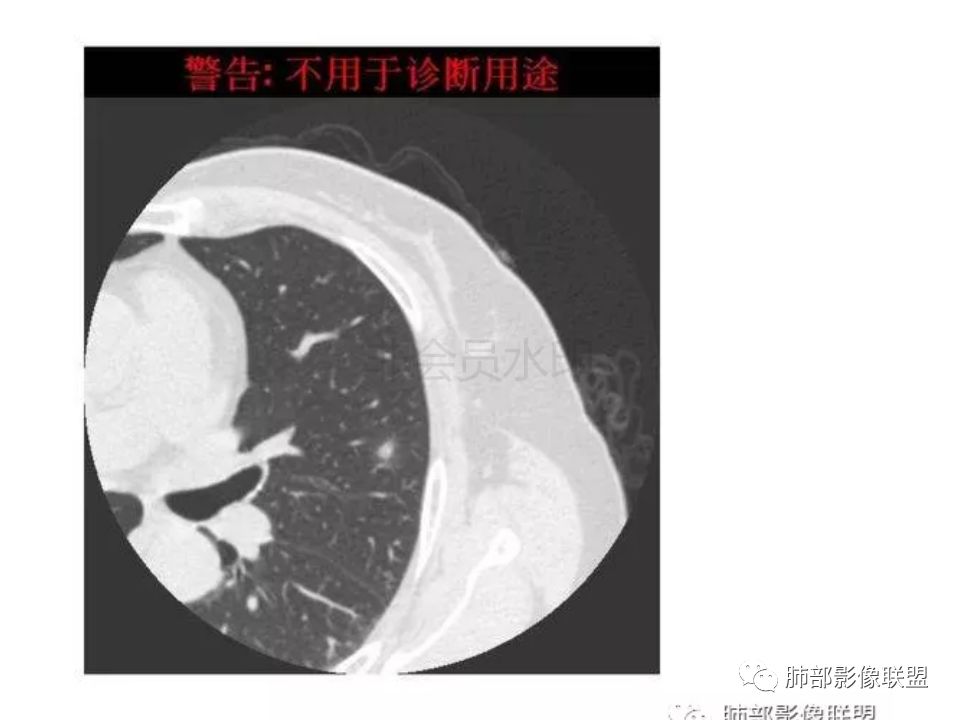

三生石上:支气管有截断,周围有晕,有空泡,腺癌?毛勤香:左肺下叶近胸膜下结节,周围磨玻璃影,边界似稍模糊,局部细支气管截断,实性区和磨玻璃区分界突然,隐约细毛刺,首先考虑感染性,隐球菌?待排腺癌MIA伴肺泡塌陷可能。常规治疗后复查。Coke with ice:IACM-Imaging :孤立胸膜下结节,其内见小泡,周围模糊的晕,晕中软毛刺,近端与血管相连,血管自然通过,气管进入结节内部一半,猜个隐球吧。第二腺癌,建议复查。田园晚风:考虑腺癌紫气东来:左肺上叶,磨玻璃实性毛刺,空泡,支气管截断,腺癌雪颜:左肺上叶结节状密度增高影,周围有晕,感觉周围模糊,有血管进入,里面有空泡征,隐约看到里面有支气管穿过,考虑炎性,隐球菌感染?腺癌待排THINKER:上叶尖后,SPN,有晕,软毛刺,无胸膜凹陷,分叶丶收缩不明显,支气管进入,远端阻塞,首选肉芽肿,PC或炎性结节,有一支血管滋养,鉴别腺癌,增殖性结核结节不支持期:左上肺结节周围有晕 晕中见细软毛刺 首先考虑隐球菌一米阳光:左肺上叶磨玻璃影,空泡,周围毛刺,月牙铲,支气管通过,周围有晕,考虑腺癌我的FY:毛刺,小空泡,磨玻璃考虑恶性崔少钢:小病灶,内有支气管,空泡征,实变不规则,放大了,感觉晕有点偏清,考虑恶性。小病灶里面有支气管是值得高度怀疑的。没有病史。彭君:左肺上叶舌段结节 周围晕模糊 内小支气管扩张 近端与血管相连 自然通过 首先考虑炎性 隐球菌?边缘月牙铲 腺癌待鉴别徐婕:左上肺结节周围有晕 ,晕中见细软毛刺 ,晕边界不太清,先考虑隐球菌张帅:左肺上叶尖后段实性病灶,以细支气管为中心,周围呈毛玻璃样影,并可见密集分布毛刺,内可见支气管征,支气管呈壁呈结节样改变,病灶周围可见血管增粗。考虑 淋巴瘤?鉴别隐球。张延军:混合型磨玻璃结节,伴毛刺,支气管截断,空泡,考虑浸润性腺癌,建议抗炎治疗后复查XGQ:支持隐球春秋:结节伴晕征,晕中毛刺,相邻小支气管近端进入,远端阻塞,近端血管相连,首先考虑隐球菌王秀仙:左肺上叶混合型磨玻璃结节,支气管截断,空泡,有毛刺,考虑浸润性腺癌,建议抗炎治疗后复查玫:左肺上叶磨玻璃结节影,薄扫见长短不一毛刺,有空泡,病灶边缘见晕征,考虑小腺癌可能,不除外炎性结节。zyf:左肺下叶近胸膜下结节,周围有晕,细软毛刺,有支气管进入,实性区和磨玻璃区分界明显,首先考虑感染性,隐球菌?查隐球菌荚膜抗原!RockJ-ason:考虑隐球采莲:左上肺靠近胸膜下实性结节影,边缘模糊,周围有晕及晕中毛刺,支气管进入通畅,有小空泡。考虑炎性病变,隐球可能性大。鉴别结核。Harvey:左肺下叶舌部小结节,边缘见磨玻璃影,边界欠清,内见支气管、管壁不光整,偏向恶性。鉴别隐球菌lmg:左肺上叶混合小结节,有晕,边界模糊,有有小毛刺。考虑炎性病变,隐球收选。AIS并肺泡塌陷带排。山河:倾向腺癌红日东升:GGO边界似清非清,内部好像不是小空泡,是小支气管腔,倾向炎性病变,常规抗炎复查除外腺癌,尤其粘液腺癌。

隐球菌感染孤立病灶与肺腺癌结节在影像上有时难分彼此,尽管隐球菌胸膜下更常见。

1.隐球菌病灶往往是实性密度结节为主伴周边边界不清楚的晕,有时可见晕内细软毛刺。

2.隐球菌病灶形态往往圆钝柔和,缺乏收缩能力,很少出现腺癌的那种胸膜牵拉和棘状突起。

3.病灶内支气管安然无恙隐球菌病灶更加多见